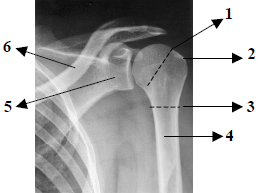

Observe atentamente a imagem radiográfica abaixo e em seguida responda à questão.

Assinale a alternativa que apresenta, em ordem numérica crescente, as estruturas assinaladas na imagem radiográfica anteriormente apresentada.

A

Colo anatômico do úmero, tubérculo maior, colo cirúrgico do úmero, úmero, colo da escápula e clavícula.

B

Colo cirúrgico do úmero, tubérculo maior, colo anatômico do úmero, úmero, colo da clavícula e escápula.

C

Colo anatômico do úmero, tubérculo menor, colo cirúrgico do úmero, tíbia, clavícula e escápula.

D

Colo cirúrgico do úmero, tubérculo menor, diáfise do úmero, úmero, clavícula e colo da escápula.